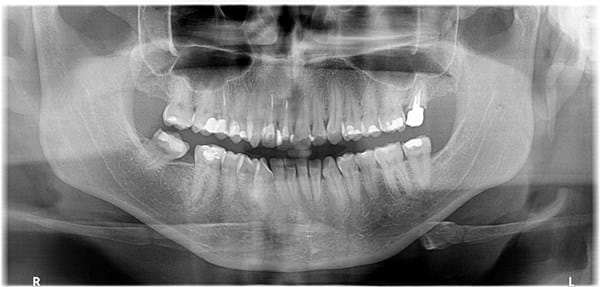

¿Cómo se ve el agujero palatino anterior en radiografía?

Quisiera saber si ¿es normal que aparezca como una sombra negra en la zona del orificio palatino anterior o si la sombra es le mismo?